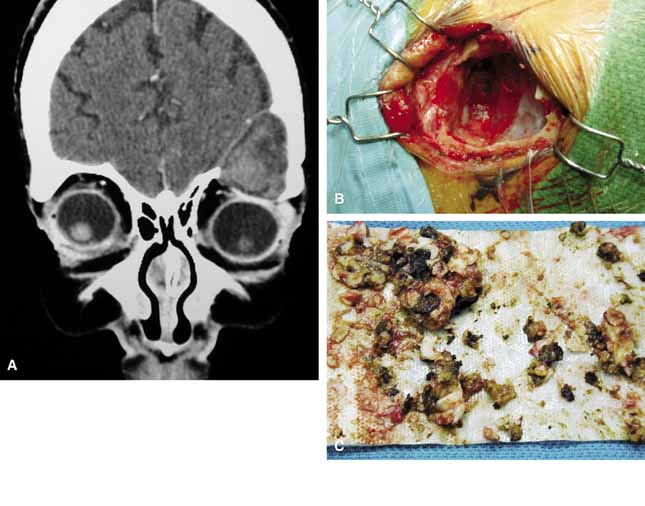

MRI is the radiographic imaging technique of choice, emphasizing high spatial resolution, fat-suppression techniques, and gadolinium contrast (Fig. 9).38 These techniques should assist in differentiating the patulous optic nerve sheath from optic nerve sheath meningioma in adults and from optic nerve glioma in children, which can be mimicked by cysts of the optic nerve sheath. Visual prognosis in these cases is guarded and the role of surgical treatment (optic nerve fenestration) is uncertain.

Fig. 9 Axial (A) computed tomography scans show enlarged right optic nerve sheath. The dilated optic nerve sheath is seen in a coronal plane (B) and is filled with cerebrospinal fluid in a T1-weighted magnetic resonance scan.